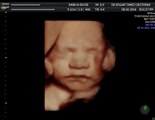

¿En qué ayuda un ultrasonido entre las semanas 11-13.6 del embarazo por un médico materno fetal?

De la mano de un médico, te daremos a conocer información muy interesante. De las dudas que normalmente tenemos, te daremos a conocer respuestas directamente de expertos en el tema.